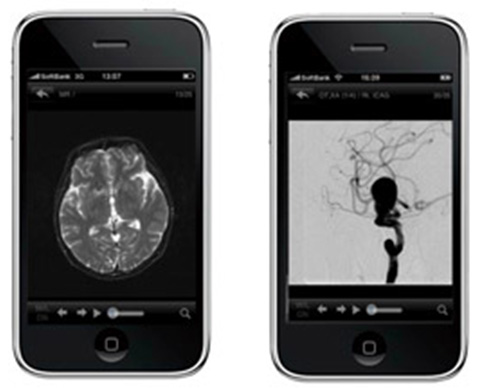

首先,就是采用近年来飞速发展的手机信息终端,我们把“无论谁,无论何时何地”都能接收到信息作为第一目标,将远程诊断治疗辅助系统「i-Stroke」作为手机(智能手机)应用程序软件进行开发(图1)。力求实现在必要时将紧急时刻所需要的图像,通过高安全性的虚拟专用网络(VPN:Virtual Private Network),使各模式(CT、MRI或DSA等)下都能简单且快速地阅读(图2)。此外,还配置了可自由构建并阅览三维图像的系统——这是迄今为止所没有的。

图2 左图MRI的图像显示。右图DSA的图像显示能以较高的分辨率高阅览